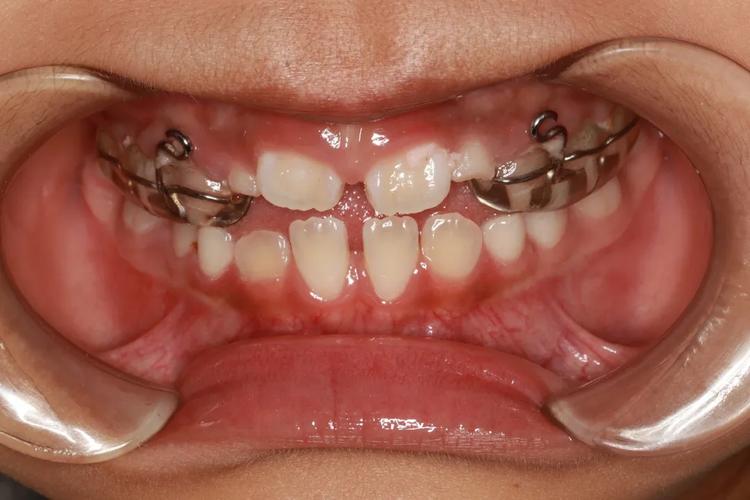

众多家长觉得早期矫正仅仅是嘴上佩戴满齿的“钢牙套”,实则并非如此。8岁这个阶段的干预方式主要是“阻断性”以及“引导性”的。极为常见的是活动矫治器,孩子于晚上佩戴或每日戴足规定时长就行;另外还有针对“地包天”的前方牵引面具,或者用于纠正不良习惯的舌栅、唇挡之类工具。此阶段的目的并非将牙齿排列得毫无瑕疵,而是消除颌骨发育的阻碍,为后续恒牙萌出营造空间,好多情形在做完一期之后,甚至无需再做二期矫正。